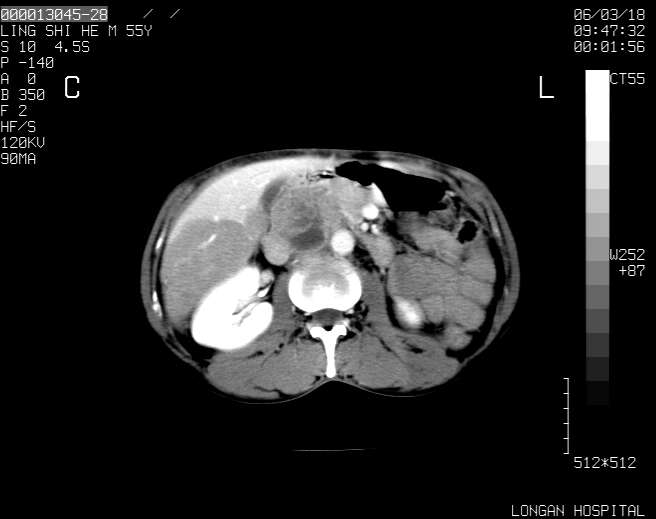

以下是引用guzhongliangddd在2006-3-21 22:13:00的发言:[br]病灶主要位于肝右叶的后份,内见异常血管,门脉主干及右支受侵{提示有癌栓形成},门腔间隙内见增大淋巴结。肝左叶内未见异常。

以下是引用zhuxinli在2006-3-22 1:23:00的发言:[br][br] 病灶主要位于肝右叶的后份,内见异常血管 .门脉右支截断,右叶前段早期强化(考虑动静脉漏),腹膜后肿大淋巴结,病灶逐渐强化,考虑为胆管细胞癌[br]